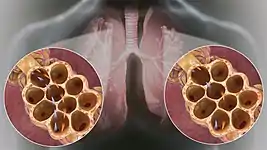

Pathological causes of tachypnea include sepsis,[5] compensation for diabetic ketoacidosis or other metabolic acidosis,[5] pneumonia, pleural effusion,[5] carbon monoxide poisoning, pulmonary embolism,[5] asthma, COPD, laryngospasm, allergic reaction causing airway edema, foreign body aspiration, tracheobronchomalacia, congestive heart failure,[5] anxiety states, haemorrhage,[5] or many other medical issues.